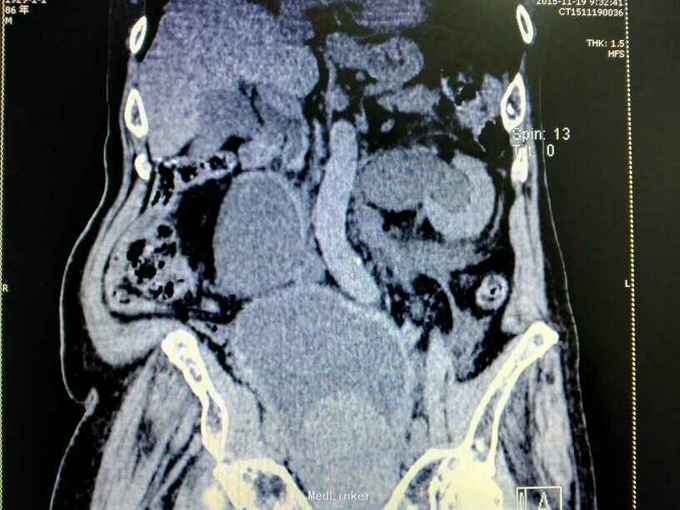

男性,87岁,进行性排尿困难10年,小便不能自解2天入院。无血尿,无发热、腰痛。一直口服藏药治疗前列腺增生症。既往无高血压、糖尿病。

腹部明显膨隆。耻骨上膀胱区扣浊。肾区无扣痛。尿常规少许白细胞。肌酐506,电解质正常。Hb116。

前列腺增生症 尿潴留 双肾积水 肾功能不全,膀胱结石,尿路感染,双肾多发囊肿。给予留置导尿,间断分次放尿后,出现肉眼血尿,持续膀胱冲洗,颜色较红,伴血凝块间断堵管。